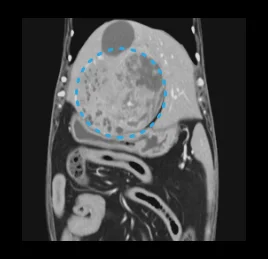

• 복부 질환

간 종양, 비장 종양, 신장 종양, 소장 종양,

• 간 종양

• 비장 종양

• 신장 종양